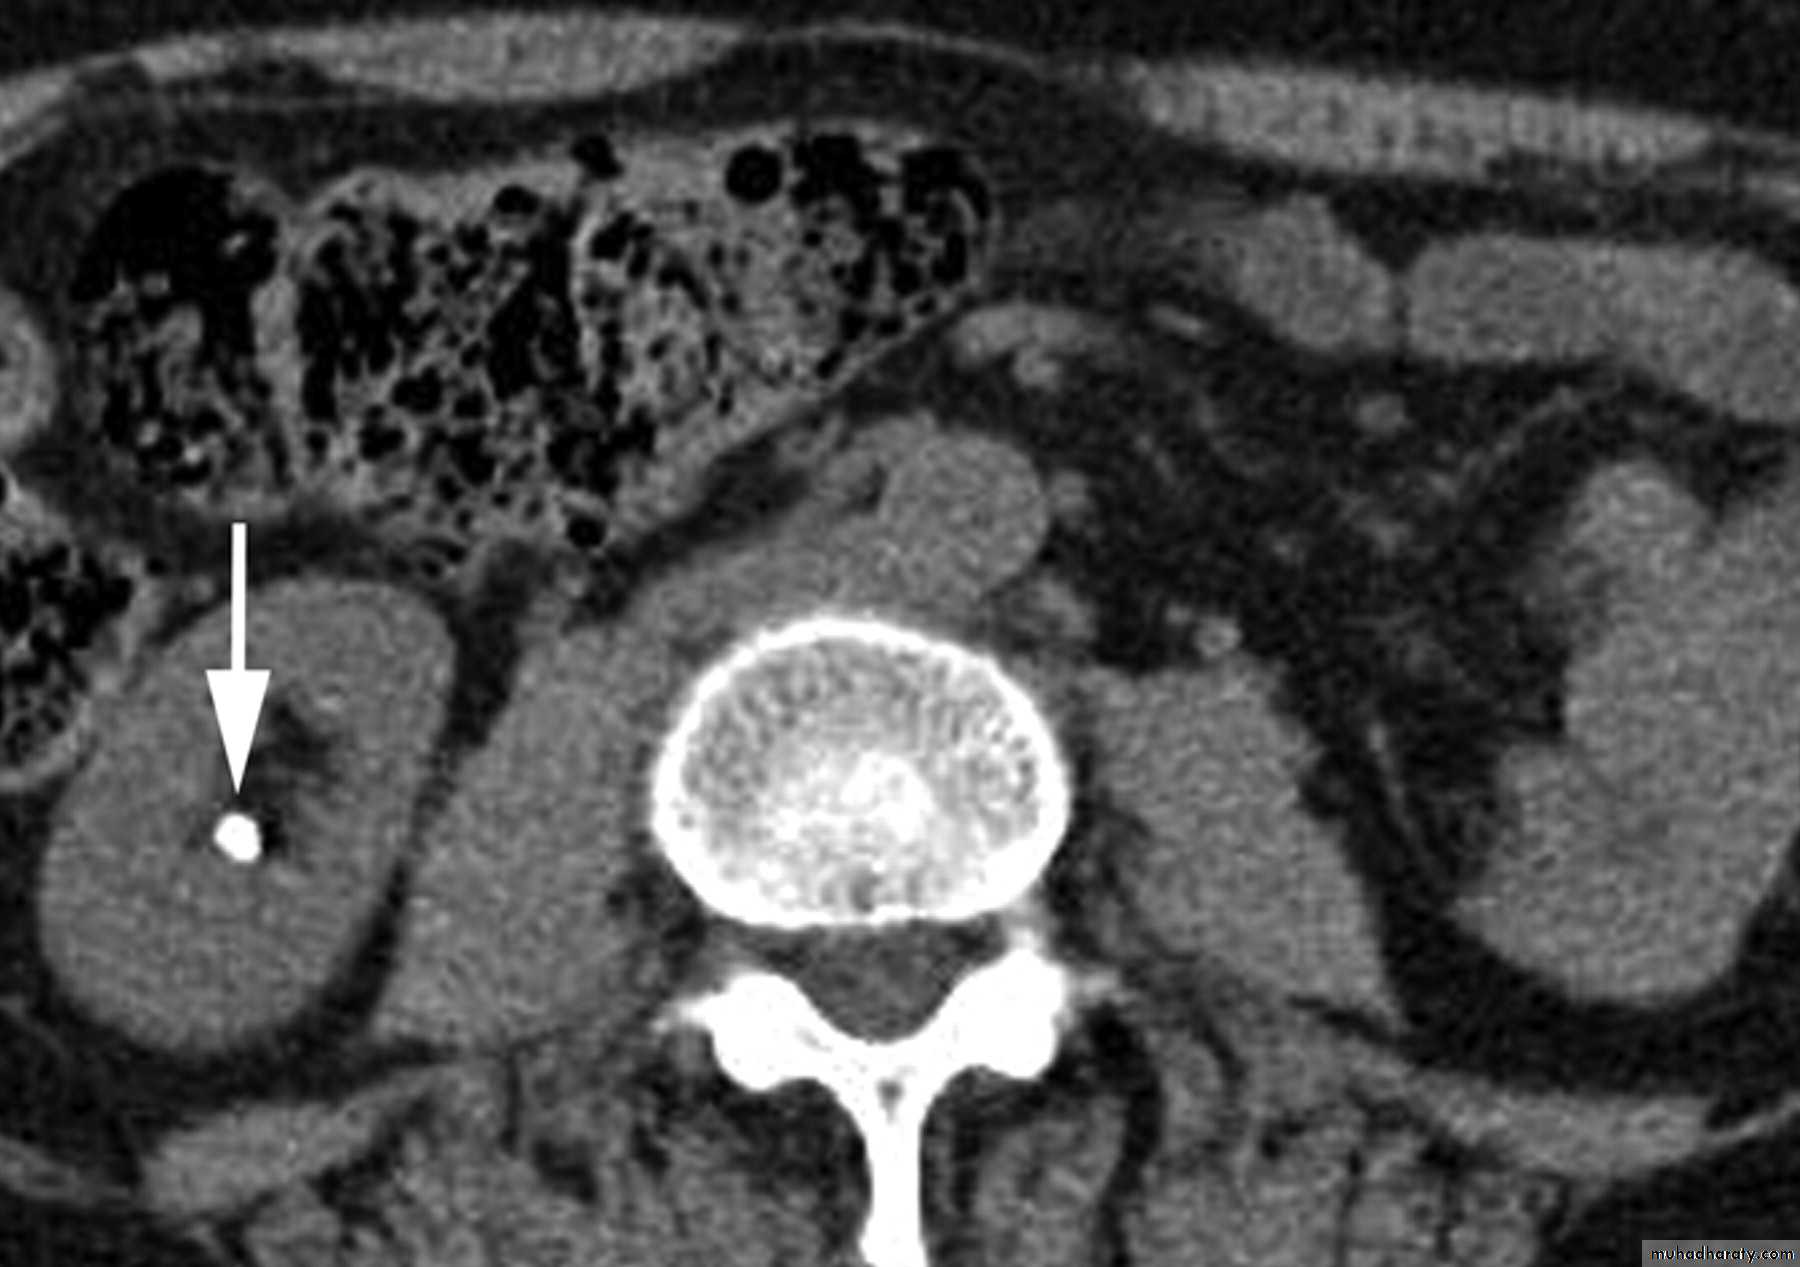

CT scans used in some hospitals during acute renal stone-Non contrast CT sensitively identify calculi and non opacified collecting system down to the level of obstruction. it has a sensitivity of 97% and specificity of 96% for detection of ureteral calculi

-Over 90% of calculi are radiopaque on plain films and virtually all on CT as very sensitive for detection of calculi, even those that appear radiolucent on plain film.

-Only pure uric acid and xanthine stones are radiolucent on plain x-ray but CAN be identified by CT or US, uric acid stones are associated with increased uric acid excretion in urine as in gout.